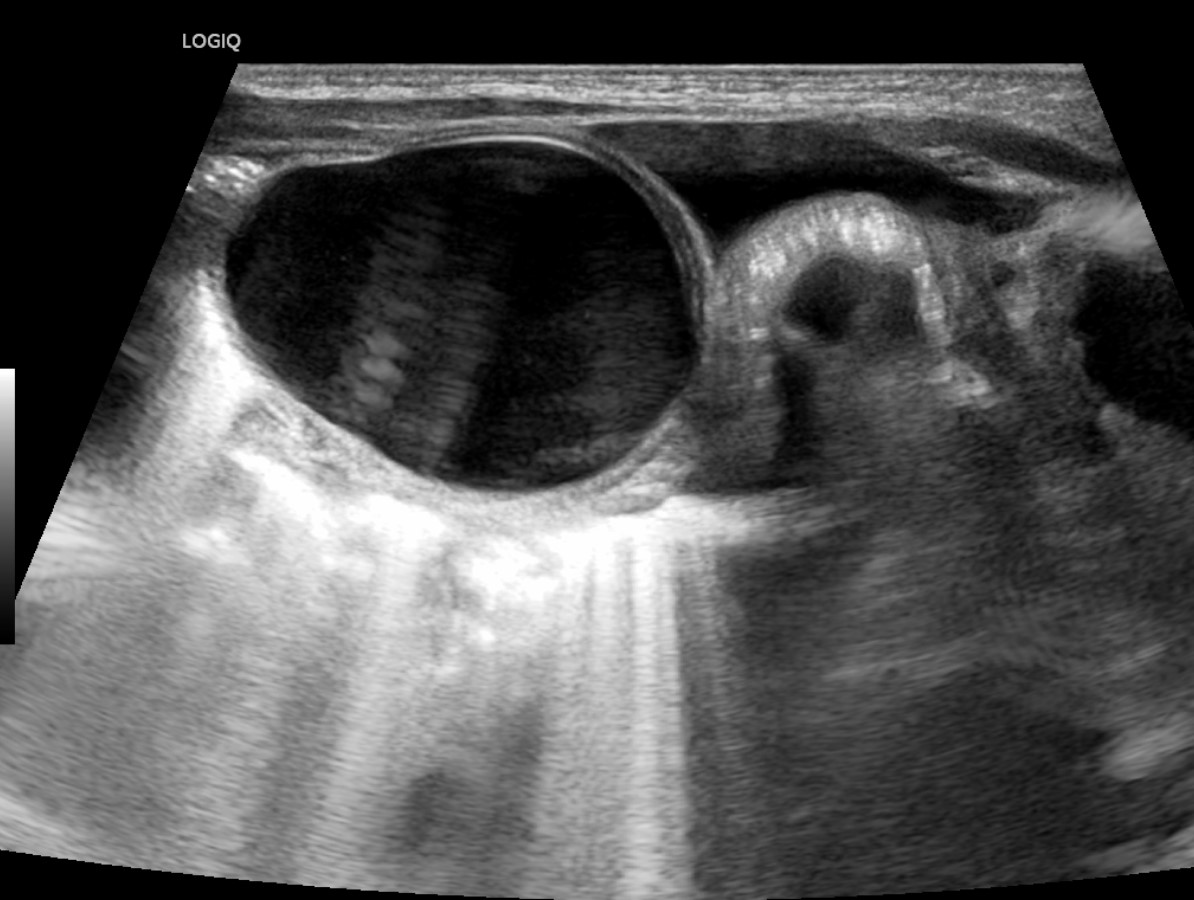

[359,Pediatric [Ped]] 1/F,Abdominal cyst was detected on prenatal ultrasound.

[Questions]  What's the diagnosis?

[Diagnosis]